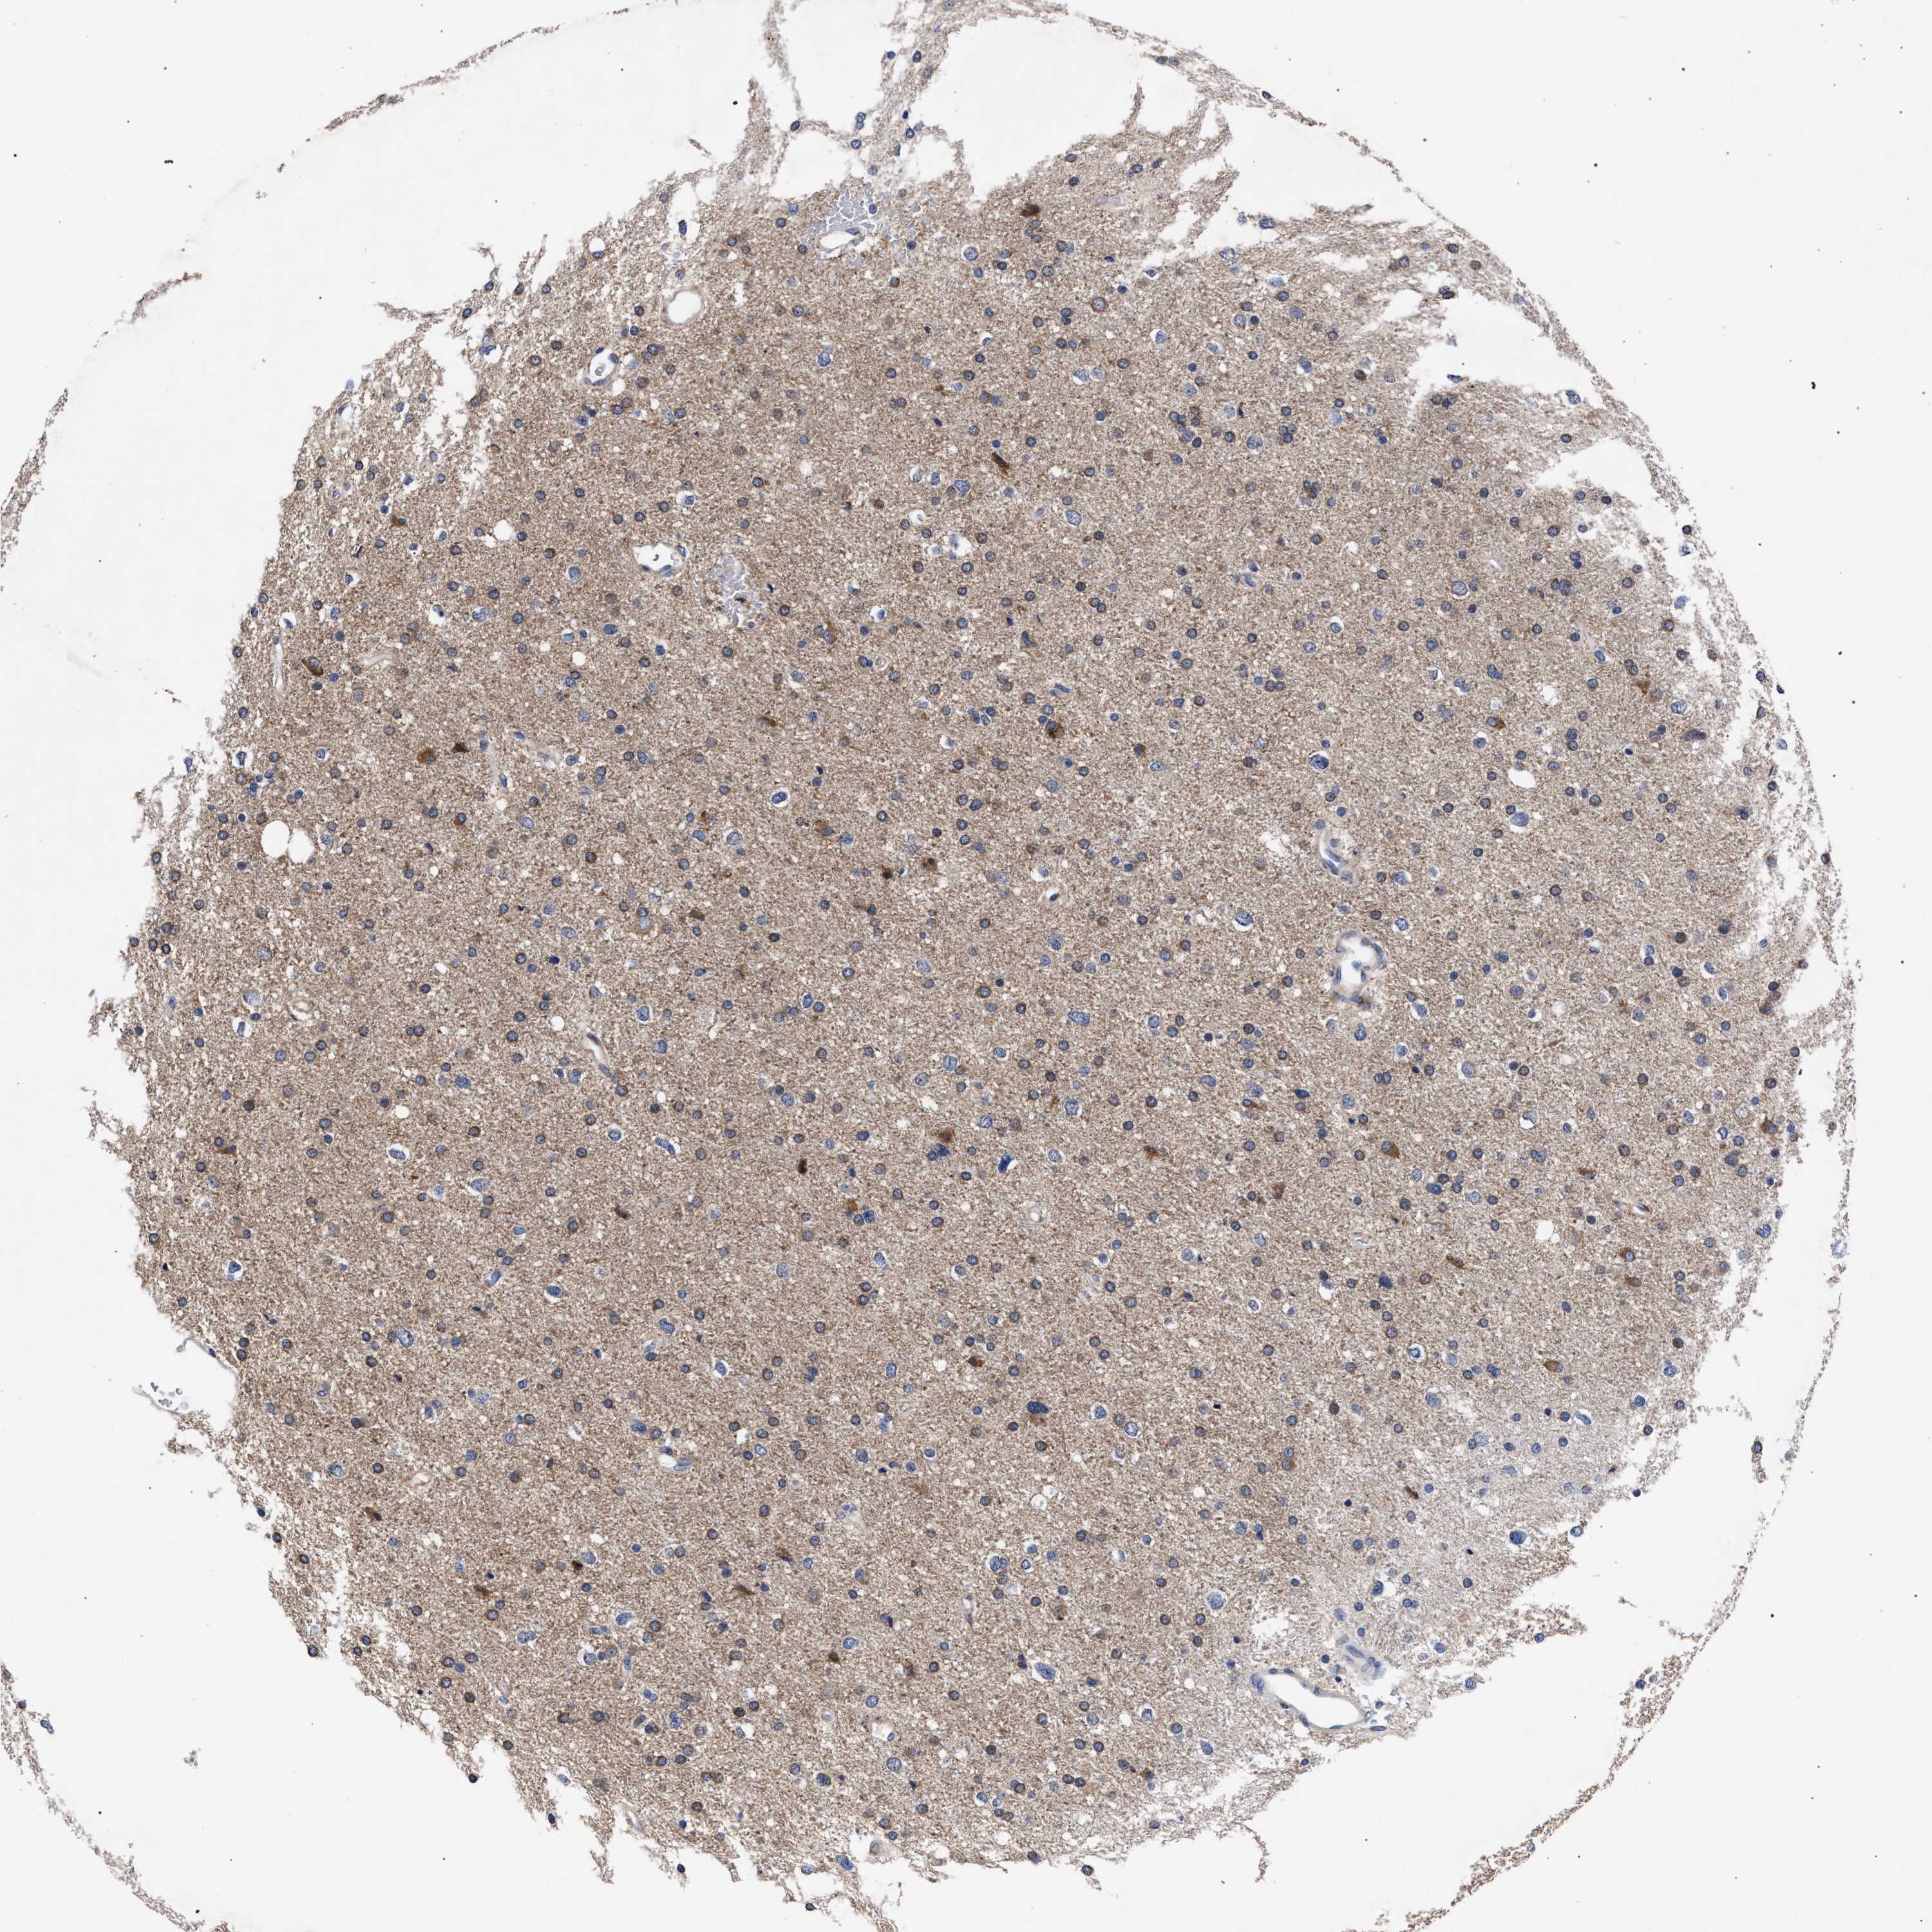

GLIOMA - Protein expressioni

A mouse-over function shows sample information and annotation data. Click on an image to view it in a full screen mode. Samples can be filtered based on level of antibody staining by selecting one or several of the following categories: high, medium, low and not detected. The assay and annotation is described here.

Antibody stainingi

Antibody staining in the annotated cell types in the current human tissue is reported as not detected, low, medium, or high, based on conventional immunohistochemistry profiling in selected tissues. This score is based on the combination of the staining intensity and fraction of stained cells.

Each image is clickable and will lead to virtual microscopy that enables deeper exploration of all samples and also displays staining intensity scores, fraction scores and subcellular localization as well as patient and tissue information for each sample.

Antibody HPA021261

Antibody HPA021325

Staining

High

Medium

Low

Not detected

Intensity

Strong

Moderate

Weak

Negative

Quantity

>75%

75%-25%

<25%

None

Location

Nuclear

Cytoplasmic/membranous

Cytoplasmic/membranous,nuclear

Glioma, malignant, High grade

Glioma, malignant, Low grade